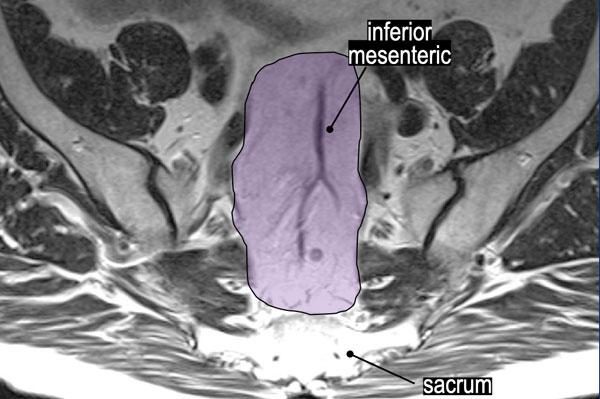

Hình ảnh MRI này minh họa

các khoang hạch bạch huyết trực tràng giữa, chậu trong, bịt, và chậu ngoài

như được phác thảo bởi Hiệp hội Nghiên cứu Hạch Bên[ref].

Những Điểm Chính:

- Các hạch chậu ngoài không phải là hạch vùng; nếu dương tính, chúng được phân loại là bệnh di căn (cM).

- Các khoang bịt và chậu trong được phân tách bởi bờ bên của thân chính của các mạch chậu trong.

- Ranh giới phía sau của khoang chậu ngoài được xác định bởi ranh giới phía sau của các mạch chậu ngoài.

Vùng màu tím làm nổi bật các hạch bạch huyết trực tràng trên và hạch bạch huyết mạc treo tràng dưới (“hạch mạc treo trực tràng cao”), đây là các hạch thuộc giai đoạn N vùng.

Yêu cầu Báo cáo:

- Chỉ định mức độ của hạch nghi ngờ gần nhất trong vùng này (ví dụ:“Hạch bạch huyết gần nhất nằm dọc theo các mạch máu trước xương cùng ở mức S2.”).

- Ghi nhận bất kỳ hạch nghi ngờ nào dọc theo chân mạch mạc treo tràng dưới.

Tác động lâm sàng:Thông tin này ảnh hưởng trực tiếp đến việc lập kế hoạch trường xạ trị và chiến lược cắt bỏ phẫu thuật.